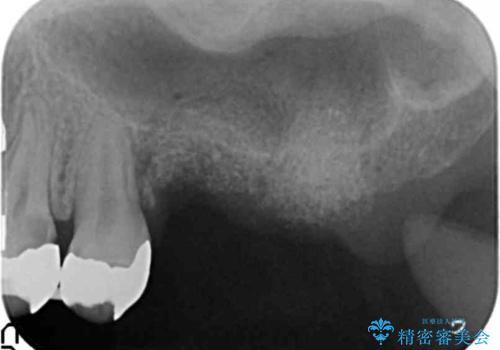

奥歯を2本失ったのち、しっかりと噛める環境へと整備するため、しっかりと骨の造成を行い清掃性を高めたインプラント治療を行っていくこととしました。

インプラントの仕上がりを見越して、ただ埋入するだけではなく長期的な予後を見込むには清掃のしやすい環境を整備することが大切です。

今回は大きく吸収してしまった歯槽骨をしっかりと造成することで、歯間ブラシを行いやすいインプラント周囲環境を整備することができました。